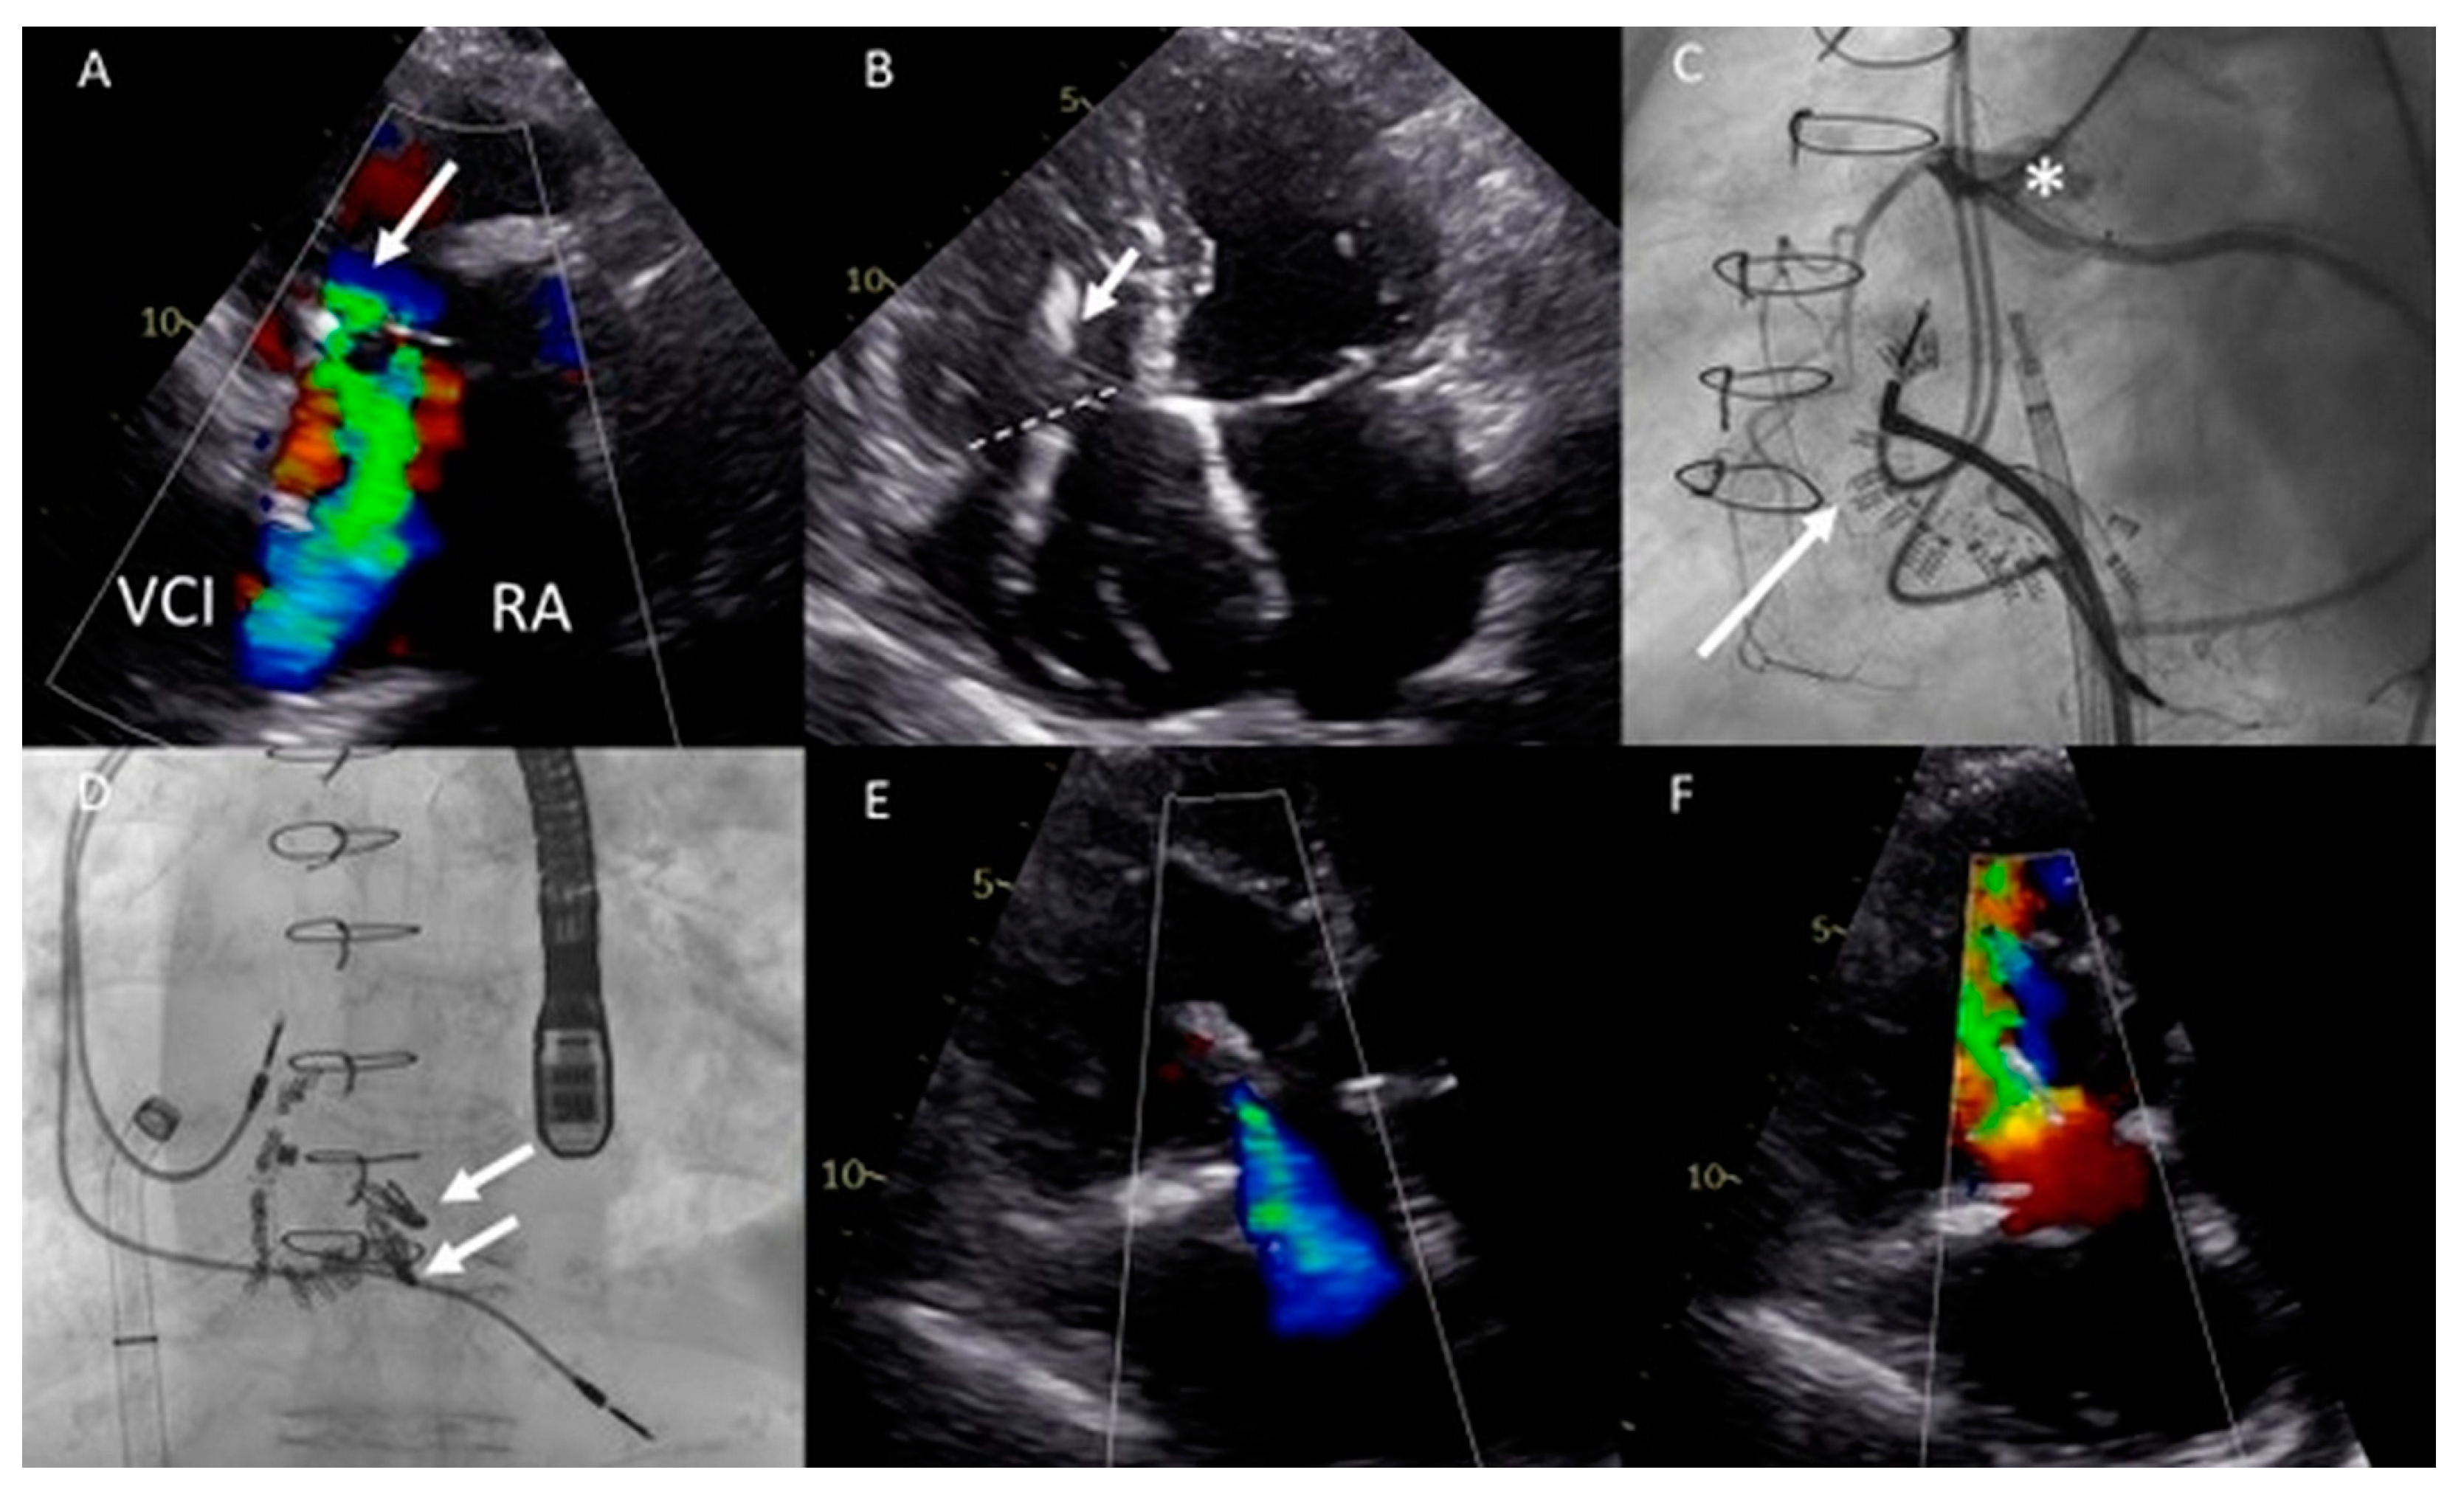

Figure 5.

(A) Distance between the right internal jugular vein and tricuspid valve (TV) measured on a computed tomography (CT) scan in a coronal plane (arrow). (B) Severely dilated mono-atrium (asterisk) on CT scan in a sagittal plane. (C) Implantation of the second XTW clip (note the first XTW clip already released) under transesophageal echocardiography (TEE) guidance. (D) Preprocedural TEE imaging of the torrential (IV+) TR. (E) Periprocedural TEE showing TR after placing the first XTW clip. (F) TEE showing the significant reduction in TR after placing the second XTW clip to grade I–II.

As a result of the severely dilated annulus and tethering, the coaptation gap was large, and simultaneous grasping of both leaflets was challenging. The TriClip system has the advanced option of independent leaflet grasping. First, the anterior leaflet (technically more challenging) was grasped and, subsequently, after minor device repositioning under TEE guidance, the septal leaflet was captured and the clip was released. The first clip was implanted near the commissure to narrow the coaptation gap so that the second clip could be implanted to treat the regurgitation (Figure 5C), which decreased to moderate (Figure 5E,F). Three weeks after the percutaneous procedure, at the outpatient clinic, the patient reported a decrease in orthopnea and exercise-induced dyspnea as the NYHA functional class was reduced from IV to III. At 17 months follow-up, the patient remained in NYHA functional class III. However, multiple heart-failure-related admissions occurred during follow-up (latest level of NT-proBNP was 8092 ng/L) and the patient developed atrial fibrillation (AF) which was treated with amiodarone.

Figure 6.

(A,B) Computed tomography (CT) scan of the thoracic cavity with the anatomical position of the dilated functional mono-atrium (asterisk) against the right thoracic wall (panel A) and bidirectional bilateral Glenn shunt (panel B) (LPA = left pulmonary artery, RPA = right pulmonary artery, LSVC = left superior vena cava, RSVC = right superior vena cava). (C) Pre-procedural transesophageal echocardiography (TEE) which visualized severe common atrioventricular (AV) valve regurgitation. (D) Anteroposterior fluoroscopic view of the two XTW MitraClips positioned in the AV valve. At the same time, it is appreciated that the delivery system is positioned through the fifth intercostal space after a right mini-lateral thoracotomy. (E) Moderate AV regurgitation after the hybrid procedure visualized with TEE.

Conventional surgical AV valve replacement or repair was considered extremely high risk due to the anatomical relation between the atrium and the thoracic wall, the extensive coronary fistulae, and the reduced ventricular function. Percutaneous AV valve replacement or repair was deemed non-feasible by the transvenous route due to interruption of the IVC with azygos continuation and sharp angulation into the mono-atrium (for a transfemoral approach). Furthermore, a transjugular approach was not feasible because of the bilateral Glenn connection. Therefore, it was decided that a hybrid procedure under general anesthesia with direct atrial access using a MitraClip delivery system (Abbott, IL, USA) was the best strategy.

The congenital cardiothoracic surgeon performed a right (mini) lateral thoracotomy in the fifth intercostal space to expose the giant mono-atrium. A double-purse string suture was placed and an incision was made to create an opening using a Safari wire for guidance and stability. The interventional cardiologist then placed two XTW clips under TEE guidance (Figure 6D), resulting in reduction in AV valve regurgitation to grade II (Figure 6E). Post-procedural TEE showed grade II regurgitation with stable position of the clips. No peri-procedural complications occurred. The patient could be discharged with adequate heart failure medication with an improvement in NYHA functional class (II). Unfortunately, the patient died after 9 months due to progressive ventricular dysfunction, worsening of the AV valve regurgitation, and heart-failure-related multi-organ dysfunction (NYHA functional class IV at the latest admission).